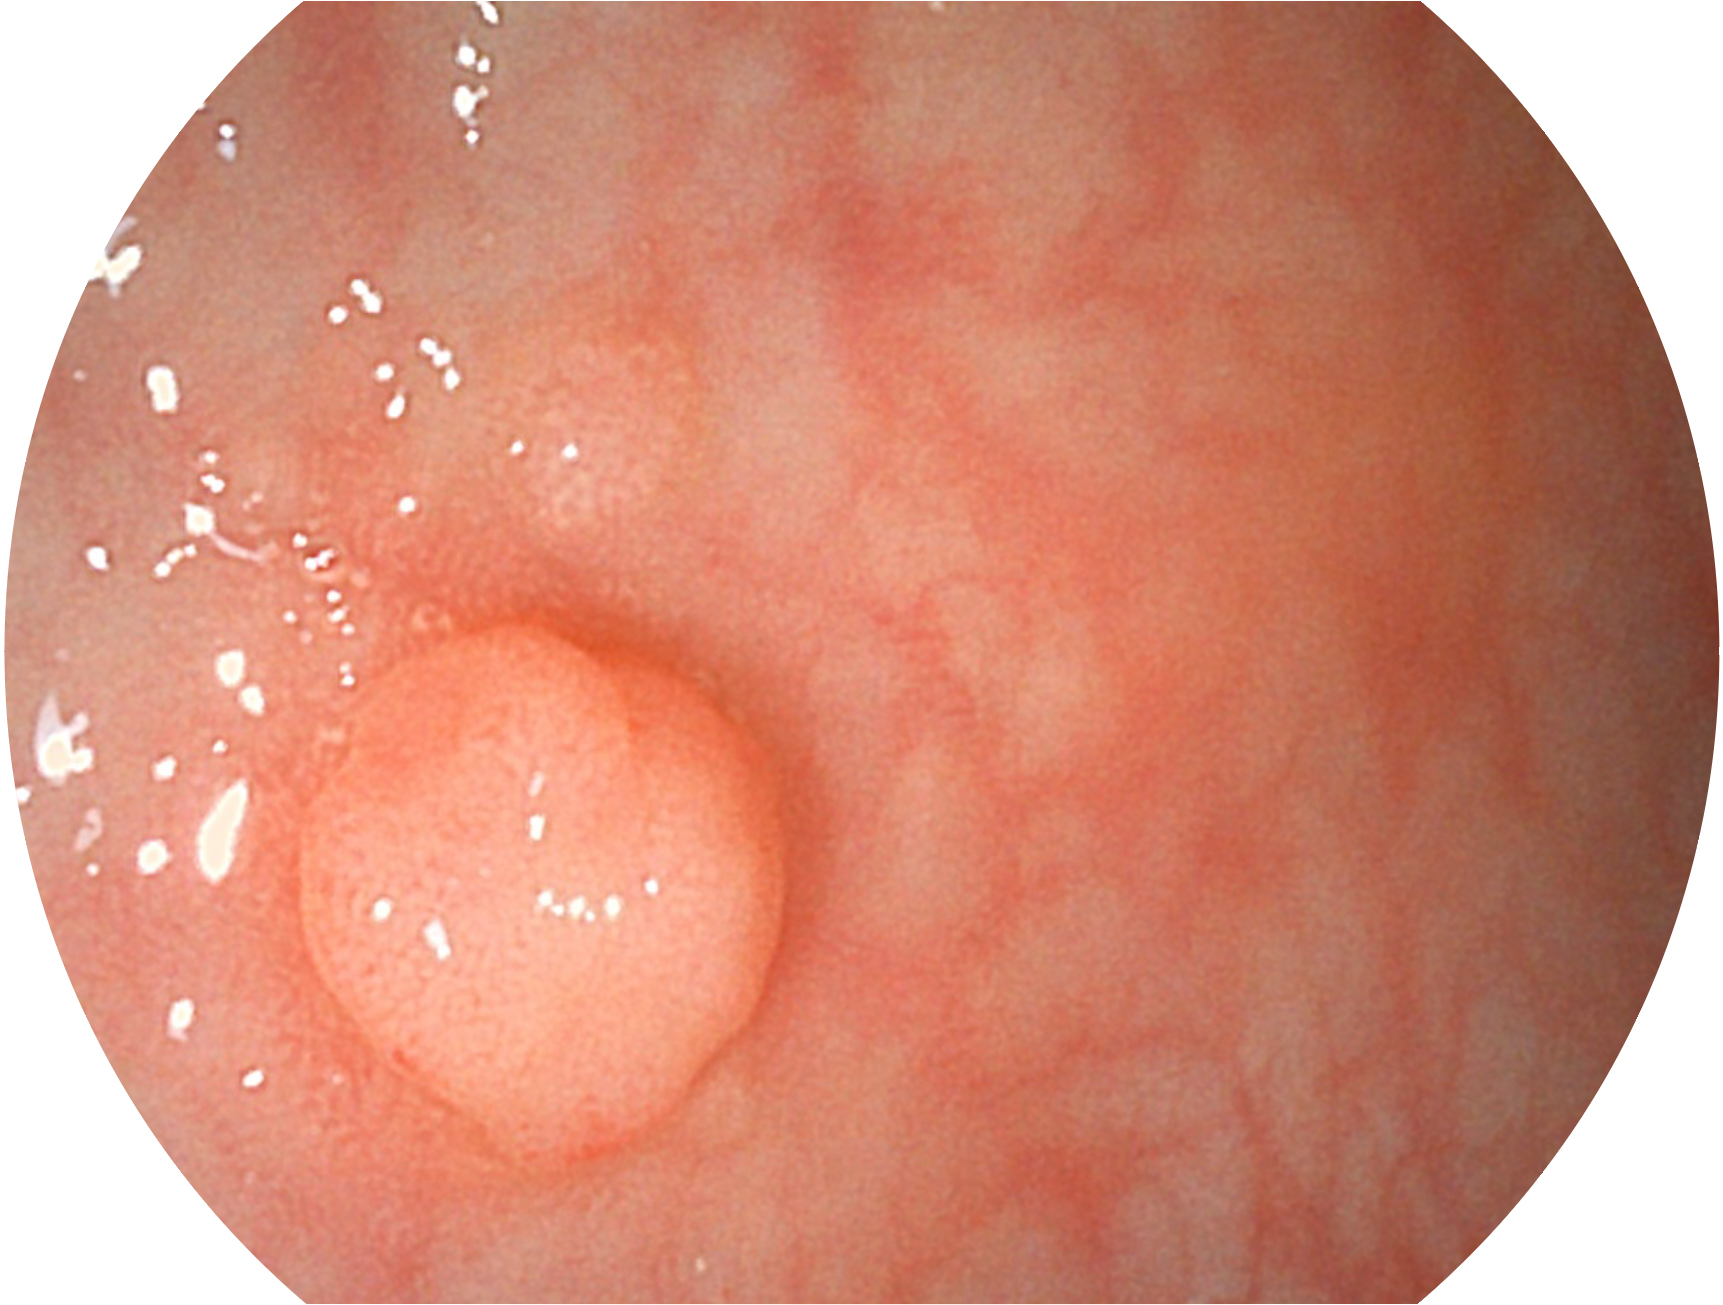

SFI技术是结合特定光谱照明与数字光谱滤波,实现高亮度特殊光成像。染色模式下,不改变粘液、食物残渣、粪液等基本颜色,在保持与白光照明相似的图像色调的同时突显了图像颜色的红白对比度,且在远距离观察的情况下具备与普通白光模式相同的图像亮度,有助于消化道疾病的大范围扫查和早癌筛查。

• 白光图像 SFI图像